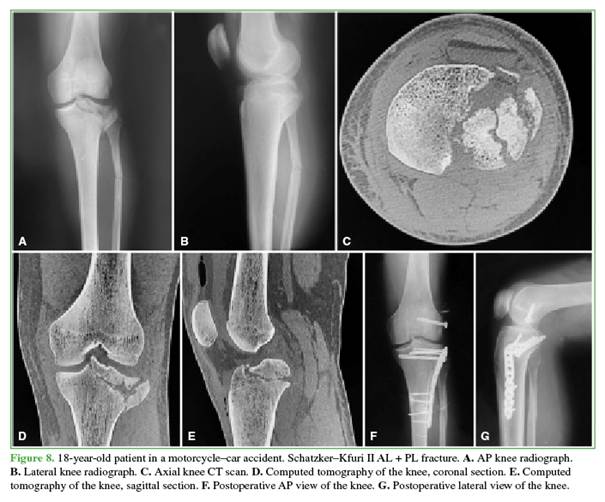

Condylar width, the medial proximal tibial angle, and tibial slope were measured and compared with the contralateral knee, all of which fell within normal parameters. All patients had <2 mm of articular depression, except for one patient with a 3-mm depression. No cases of nonunion or displacement of the epicondylar osteotomy bone block were observed (Figures 7 and 8).